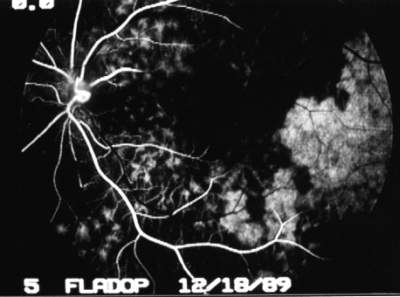

Abb. 15 Phase der diffusen Aderhautfüllung (FLADOP, IOD = 45 mmHg) |

Die Spätphase der Aderhautfluoreszenz unterscheidet sich nicht mehr von der normalen Fluoreszenzangiographie. In der diffusen Färbung der Choriokapillaris stellen sich die jetzt fluoreszeinfreien Aderhautgefäße als unscharfe, dunkel Streifen dar (Negativ-Darstellung der Aderhautgefäße). Fluoreszenzangiographische Befunde, wie z.B. pathologische Hyperfluoreszenzen oder Fensterdefekte, können genauso wie bei der konventionellen Angiographie erhoben werden (Abb. 15) . |